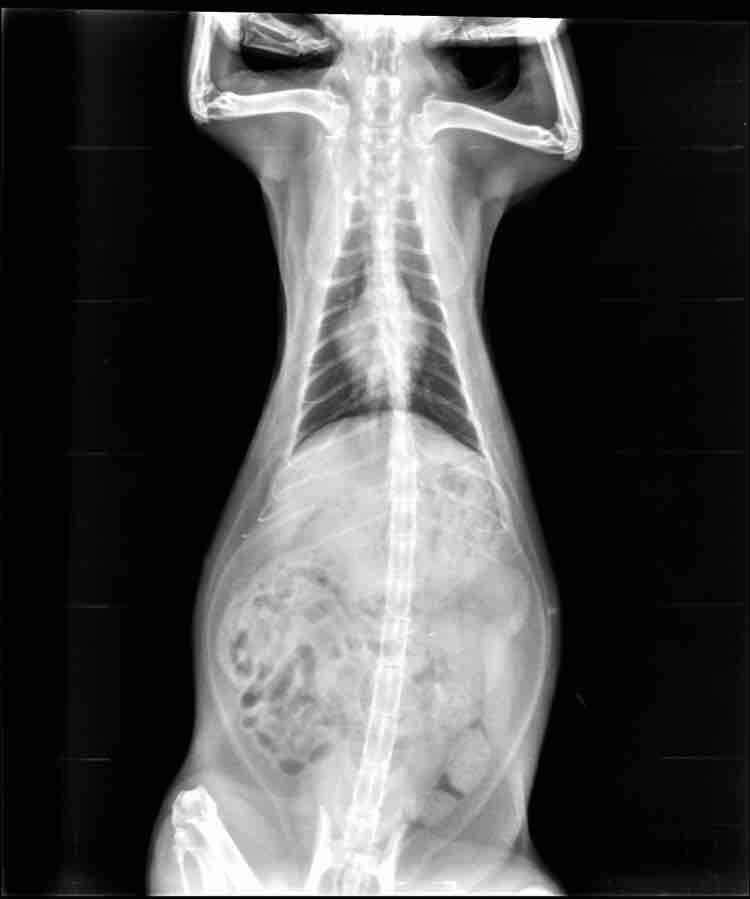

Could you please explain in what ways/way a fast breathing rate of a cat could be related to overweight? Does it mean some sort of serious heart/lung problem or could it just be simple and simply resolved by losing weight?

The excess fat can make breathing harder, and due to that, the cat may breath faster to get sufficient oxygen around the body. The cat's lungs are struggling to inflate with fresh oxygen due to the excess weight, and if the cat doesn't have enough oxygen, they can breath faster to get it. Certainly weight loss can help with breathing problems, but the breathing problems can be caused by heart or lung problems. Only your vet who sees Sofia in person can make this determination. I hope this helps.